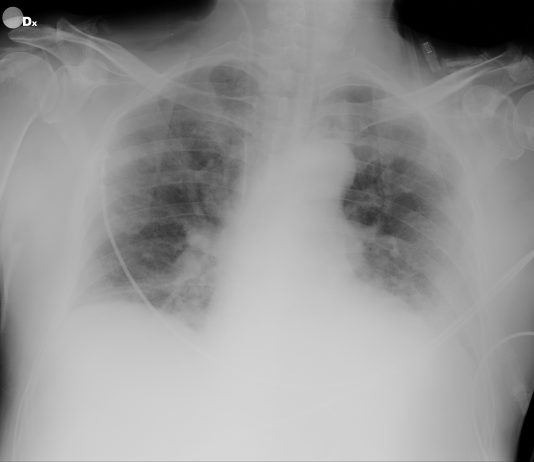

Patient presented

for cough and dyspnea for 5 days, not responding to antibiotics. Potential risk

for SARS-CoV-2: he traveled from Florence...